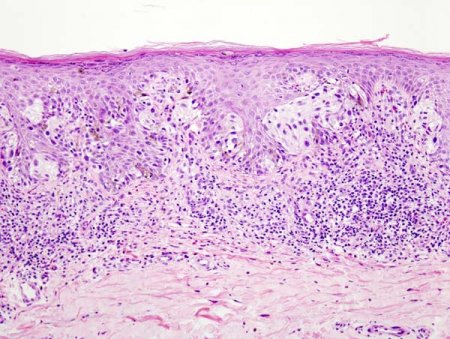

Клінічно злоякісна меланома виглядає як щільний пухлинний вузлик інтенсивно чорного кольору, іноді з блакитнуватим відтінком. Рідше зустрічаються безбарвні меланоми рожевуватого кольору, позбавлені пігменту вузлики. Розміри пухлини різні: від 0,5 до 2-3 см у діаметрі. Нерідко пухлина має пошкоджену поверхню, що кровоточить, і ущільнену основу. На ранніх стадіях злоякісна меланома виглядає більш безневинно, і потрібен великий досвід для того, щоб відрізнити її від доброякісного пігментного невуса. Існують два варіанти лікування меланом: чисто хірургічний метод і комбінований.

Нерідко хворий звертається з приводу збільшених лімфатичних вузлів тієї чи іншої ділянки. При ретельному опитуванні вдається встановити, що раніше пацієнту з косметичною метою була видалена “бородавка”, яка була злоякісною меланомою, що підтверджується гістологічним дослідженням.